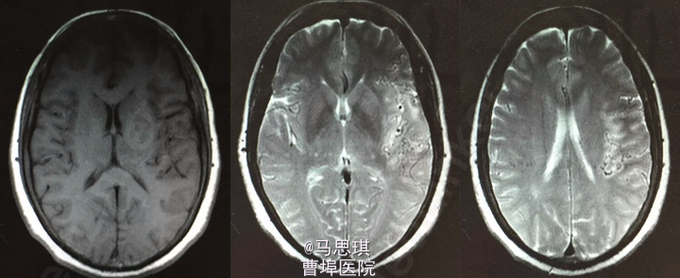

入院诊断为:“脑梗塞?” 患者有溶栓指征,但患者家属拒绝溶栓。 治疗: 氯吡格雷75mg Qd 拜阿司匹林0.1 Qd 立普妥 20mg qd 胞磷胆碱0.2tid 依达拉奉30mg ivgtt bid 康复治疗 入院第二天行MRI及MRA检查。 头部MRI:左侧额颞岛叶见片状稍长T2稍长T1信号灶,其内见较多增粗、增多血管影,原因?考虑:血管畸形所致左侧额颞岛叶缺血梗塞性改变?血管炎性病变或脑炎待排? 头颅MRA:左侧额颞岛叶见较多增粗、增多的血管影,右侧额颞顶交界区血管影稍增多。左侧胚胎型大脑后动脉。 入院第四天行头颅增强CT及CTA。 头颅增强CT:左侧颞叶见片状低密度影,其内见大小约0.7x1.6cm片状高密度影,与前片比较,见范围加大,考虑系梗塞后伴出血,血管畸形。增强扫描见左侧额颞叶较多迂曲扩张的血管影。 CTA:左侧额颞岛叶区域见大脑中动脉岛叶段,侧裂段及分叉段分支明显增多,部分迂曲、扩张,呈杂乱走行的血管团样改变,考虑血管畸形可能;右侧额顶交界区血管影稍增多。双侧颈内和基底动脉及大脑前中后动脉显示清晰,其大小、走行、信号未见确切异常,各血管壁光整,管腔未见确切狭窄,走行自然。 发现出血后,停用双联抗小板治疗,并加做DSA DSA示:左侧颈外动脉分支脑膜中动脉血管畸形,与颈内动脉,椎动脉无明显交通 修正诊断为: 左侧额颞岛叶脑梗塞并梗塞后出血; 左侧脑膜中动脉血管畸形 动脉粥样硬化症 上呼吸道感染